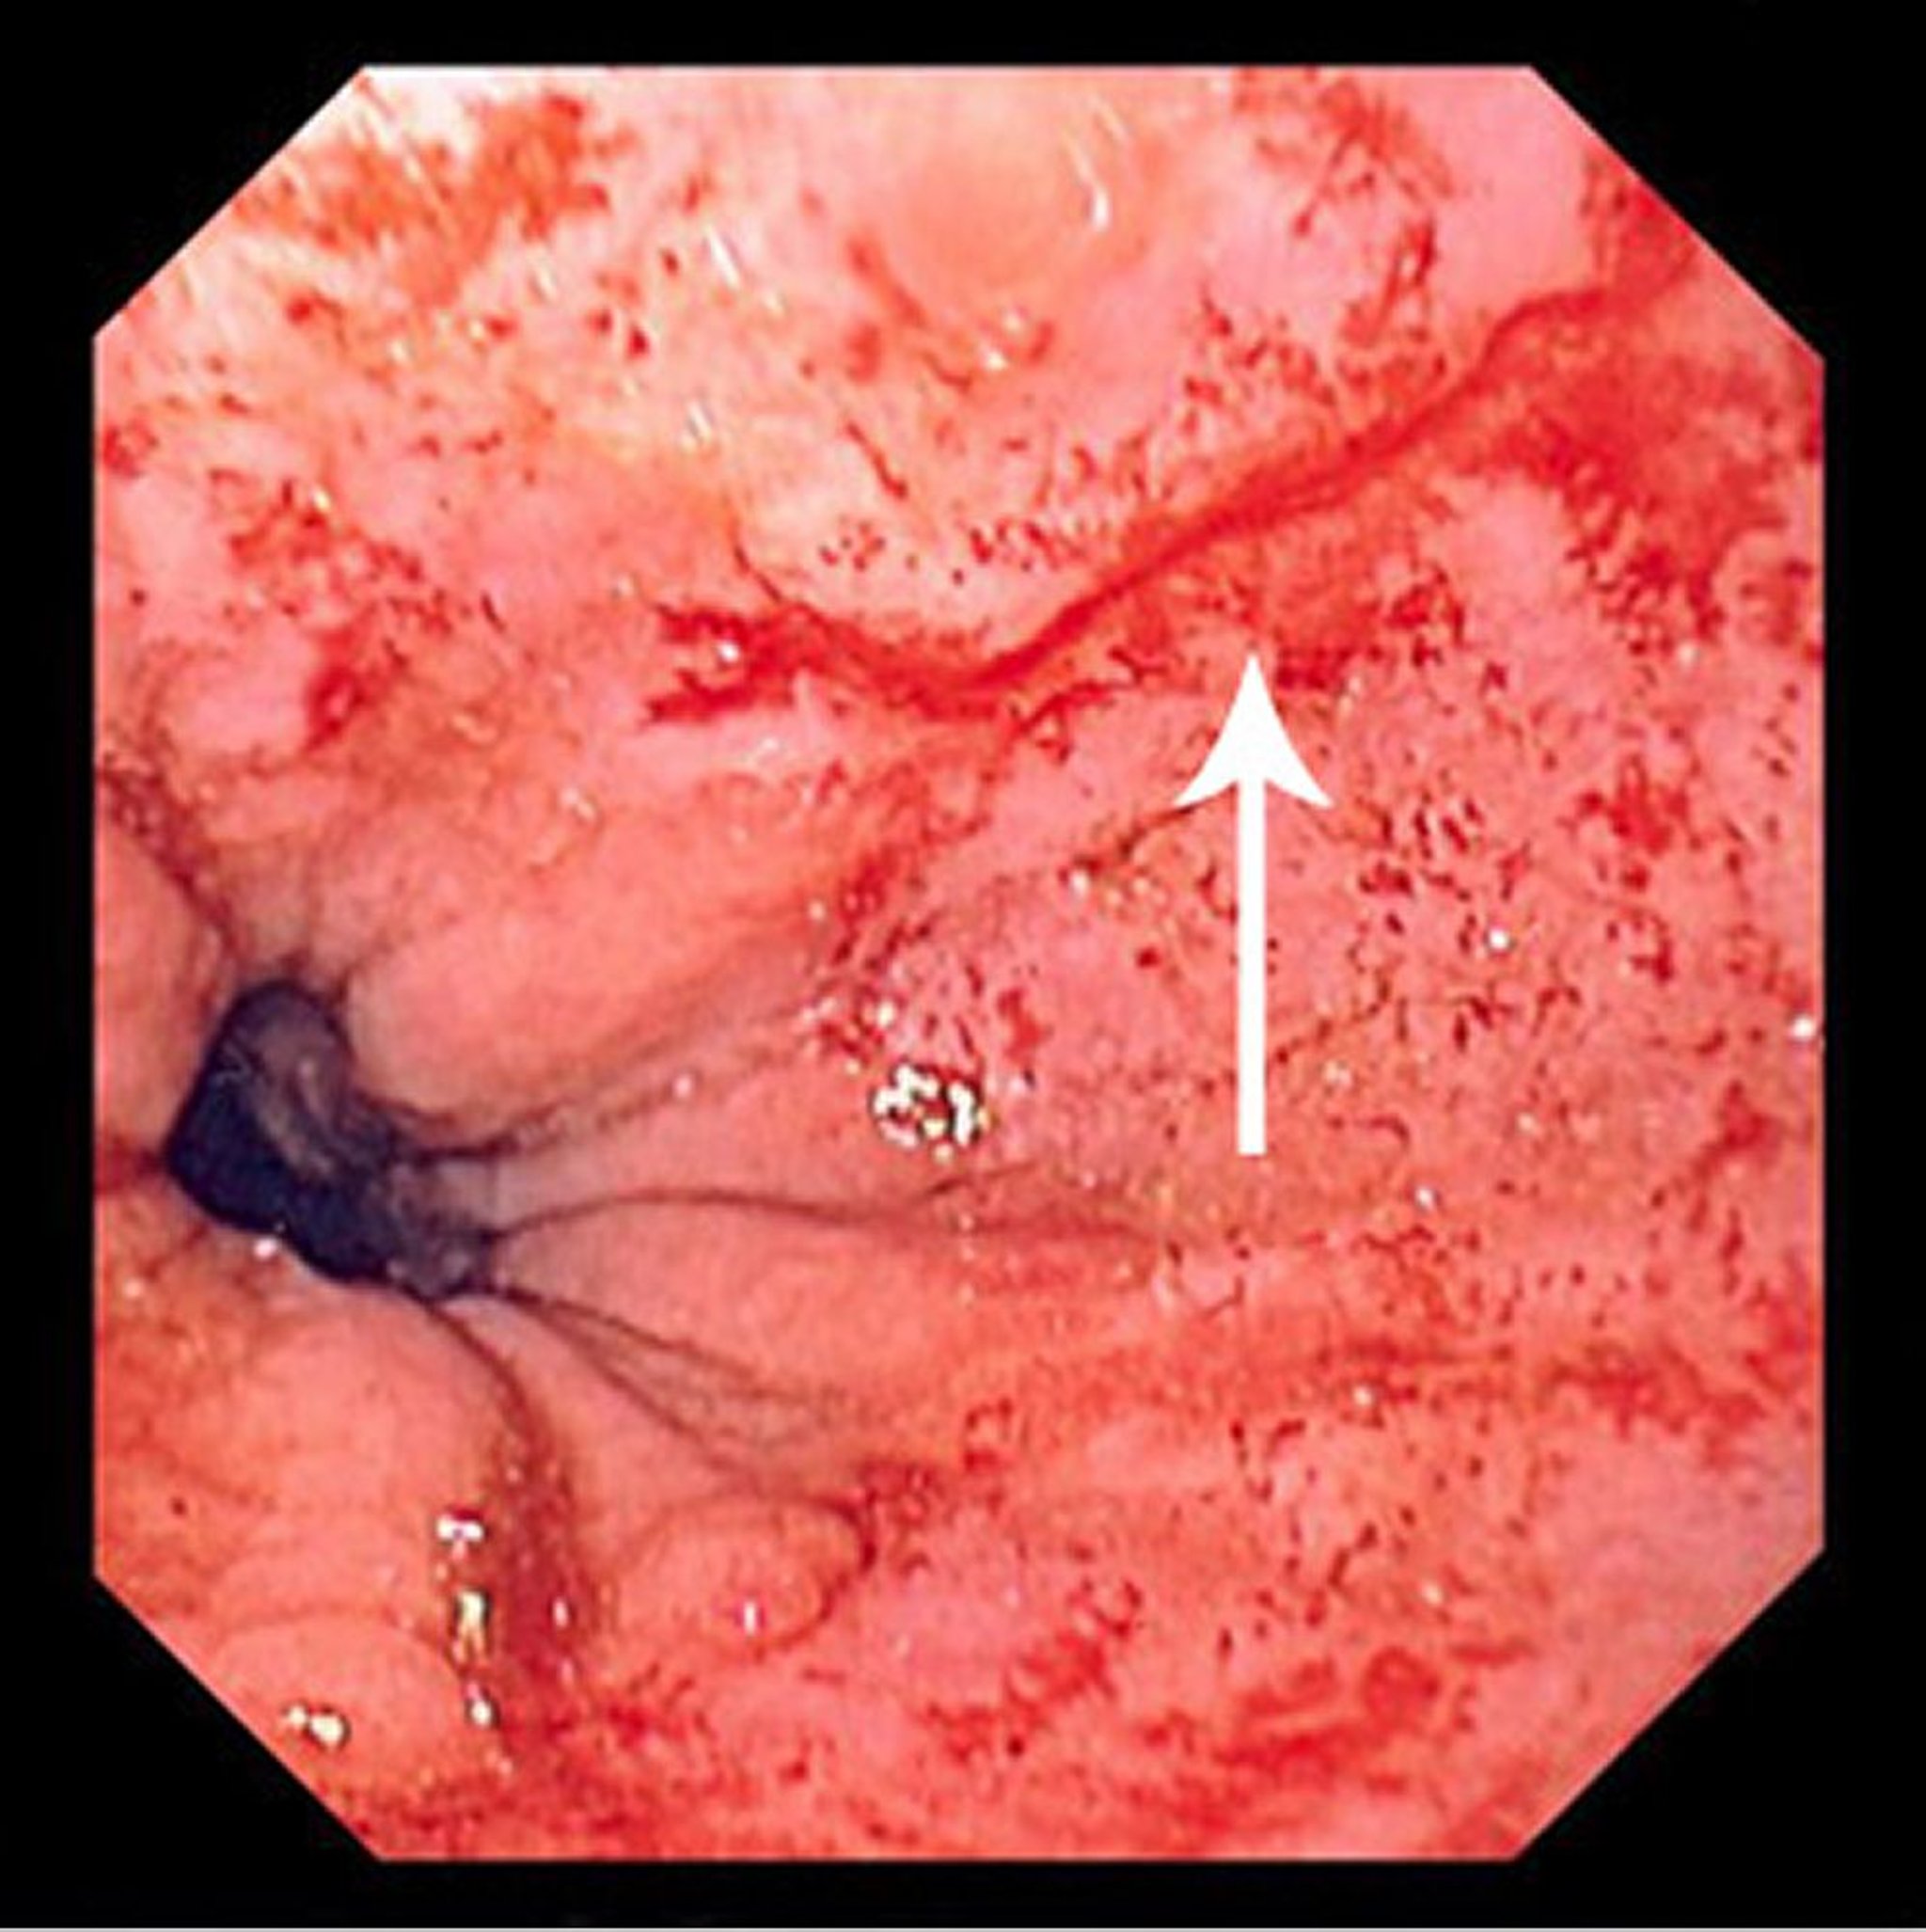

マロリー-ワイス症候群

この写真には、マロリー-ワイス症候群による細い裂傷(矢印)が写っています。

Photo provided by David M.Martin, MD.